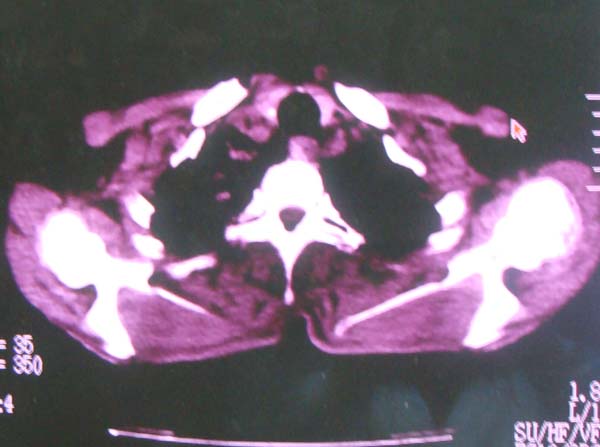

以下是引用zhangzhongshou在2008-2-15 22:25:00的发言:[br]片子照得不清,基本考虑1、细支气管肺泡癌2、亚急性血行播散型肺结核。请结合临床。片子细节显示不清,无法提供进一步意见。

以下是引用杀毒软件在2008-2-15 22:34:00的发言:[br]小叶中心性肺气肿。两肺弥漫性病变,肺泡微石病,过敏性肺炎,尘肺2期,特发性肺纤维化都有可能。[br]不象肺泡癌。